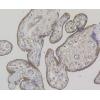

Fig3: Paraformaldehyde-fixed, paraffin embedded (mouse brain); Antigen retrieval by boiling in sodium citrate buffer (pH6.0) for 15min; Block endogenous peroxidase by 3% hydrogen peroxide for 20 minutes; Blocking buffer (normal goat serum) at 37℃ for 30min; Antibody incubation with (TREM2) Polyclonal Antibody, Unconjugated at 1:200 overnight at 4℃, followed by operating according to SP Kit(Rabbit) (sp-0023) instructionsand DAB staining.